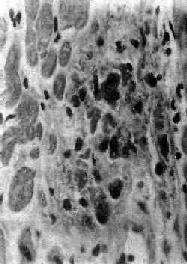

Aschoff 小体体积颇小,一般显微镜下才能看见(图8-19),多发生于心肌间质、心内膜下和皮下结缔组织;心外膜、关节和血管等处少见。在心肌间质内者多位于小血管旁,略带圆形或梭形,其中心部为纤维素样坏死灶,周围有各种细胞成分:①Anitschkow细胞:胞浆丰富,嗜碱性,核大,呈卵圆形、空泡状。染色质集中于核的中央,核的横切面状似枭眼;纵切面上,染色质状如毛虫。②Aschoff巨细胞(Aschoff giant cell):含有1~4个泡状的核,与Anitschkow细胞相似,胞浆嗜碱性。以上两种细胞的来源尚有争论,但现代标记技术证明其为巨噬细胞源性。③小体内还有少量淋巴细胞(主要为T细胞)和个别中性粒细胞。此期经过约2~3个月。

图8-19 Aschoff小体

主由Anitschkow细胞、Aschoff巨细胞和淋巴细胞等组成,中心部常有纤维素样坏死物